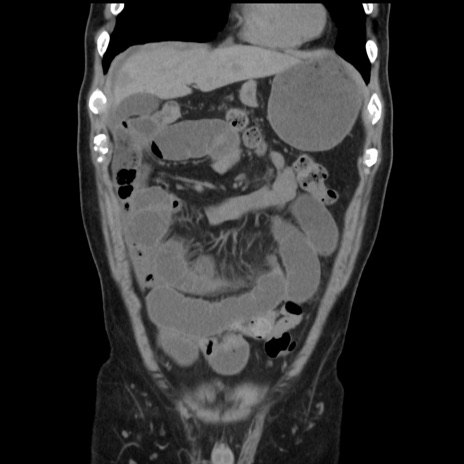

症例16(冠状断像)

【症例】 70歳代男性

【主訴】 腹痛、嘔吐

【現病歴】 約1ヶ月前より間欠的に腹痛と嘔吐あり、当院消化器内科を受診したところCTで多発する肝臓のLDAを指摘され、精査中であった。以降は消化器症状は安定していたが、2日前より嘔気と腹痛があり、同日より排便・排ガスが消失した。改善認めず、 本日、救急外来を受診した。

【身体所見】意識清明・会話良好、BT 36.3℃、BP 127/80mmHg、 P 80bpm、腹部:膨満あり、平坦・軟、上腹部正中および下腹部正中に圧痛あり、反跳痛なし、筋性防御なし。

【データ】WBC 7200、CRP 0.77